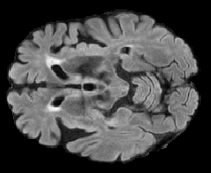

In order to analyze qualitatively the results of our generator, we extract slices with different WMHs loads, Table 4 shows the reconstruction results for three different levels of loads. As we can see in the first row, both methods produce a similar response in regions with a low load of lesions, it can be observed that generated images are similar to the real FLAIR images in the left, and these not present evident structural distortions. However, it can be noted images exhibit blurred effects, which can be due to L2 based optimization, more complex generative networks with adversarial loss optimization as GANs tend to eliminate blurred effect but at the expense to produce structural distortions. In the application presented in this work it is important to preserve the structural information, thus, our L2 based optimization present a good balance between preserve structural information and blurred effects. In the second and third column, it can be observed the performance of both methods when facing the presence of lesions, as can be seen, both methods have a good response to large and contiguous lesions. It also can be noted both methods tend to produce poor performance in small and diffuse WMHs marked in red, note, these lesion do not exhibit identifiable patterns in T1 images, however it can be seen that our proposed method is more sensitive to these patterns which enable to highlight some small regions as those marked in green.

FLAIR T1 Offline synthesis Proposal

[Uncaptioned image] [Uncaptioned image] [Uncaptioned image] [Uncaptioned image]

Table 4: Results of Generation for all the proposed methods,